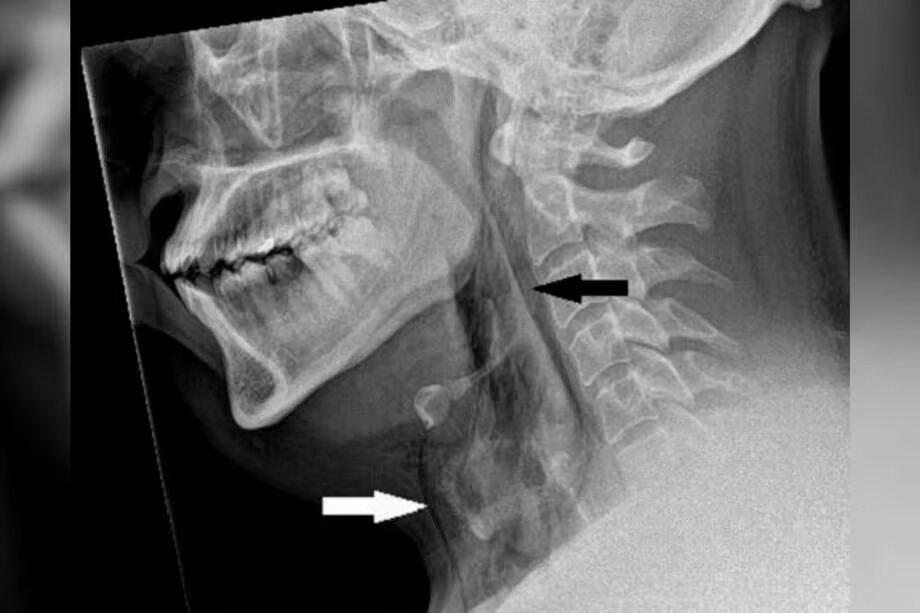

Una radiografía posterior confirmó un enfisema quirúrgico, con el aire atrapado entre las capas de tejido profundo y acumulado en el espacio del pecho entre los pulmones. Aunque los médicos determinaron que no se necesitaba cirugía, el hombre permaneció en el hospital durante dos días para garantizar la estabilidad de sus signos vitales. Fue dado de alta con analgésicos y la recomendación de evitar actividades físicas intensas.